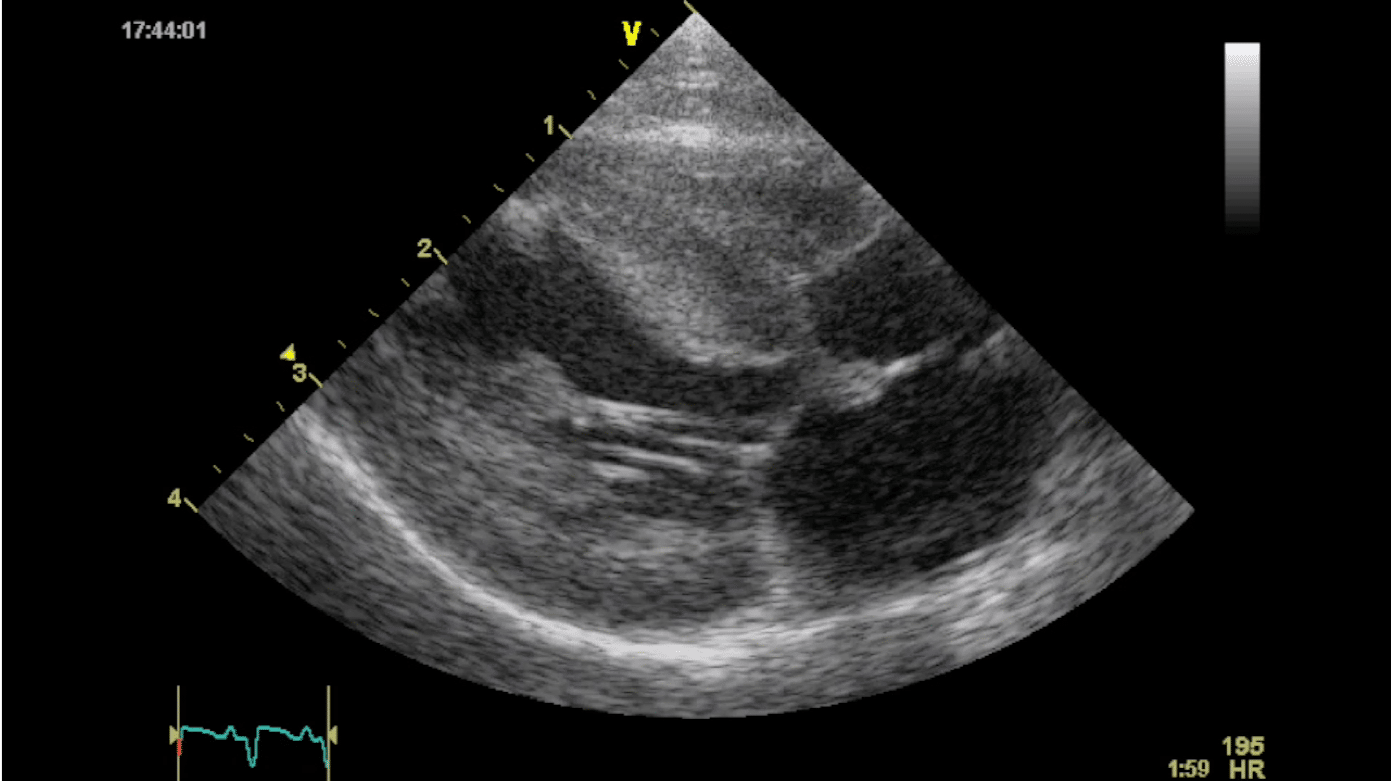

Echocardiography is the gold standard for diagnosing hypertrophic cardiomyopathy in cats. Elizabeth Rozanski, DVM, ACVIM, ACVECC, and colleagues at Tufts University knew that several barriers to this test exist including cost, proximity to a boarded cardiologist, and the skillset and equipment required to perform a full echocardiogram. They were also aware that focused cardiac ultrasound (FCU) was gaining popularity in human hospital emergency rooms as a quick way to assess patients for serious cardiac conditions. Dr. Rozanski wanted to determine if a non-specialist practitioner (NSP) could be trained to perform FCU to increase detection of occult heart disease in cats.

Dr. Rozanski and her team developed an FCU protocol and trained 22 NSPs to perform the procedure. The NSPs screened 289 cats without signs of heart disease. All patients had follow-up echocardiograms by a board-certified cardiologist.

Dr. Rozanski found that the NSPs were very good at detecting moderate and severe heart disease in the study population. They were less skilled at detecting mild disease, but Dr. Rozanski was encouraged by the results and hopes more practitioners can learn FCU and incorporate it into their practice. Dr. Rozanski published her results in the Journal of Veterinary Internal Medicine.